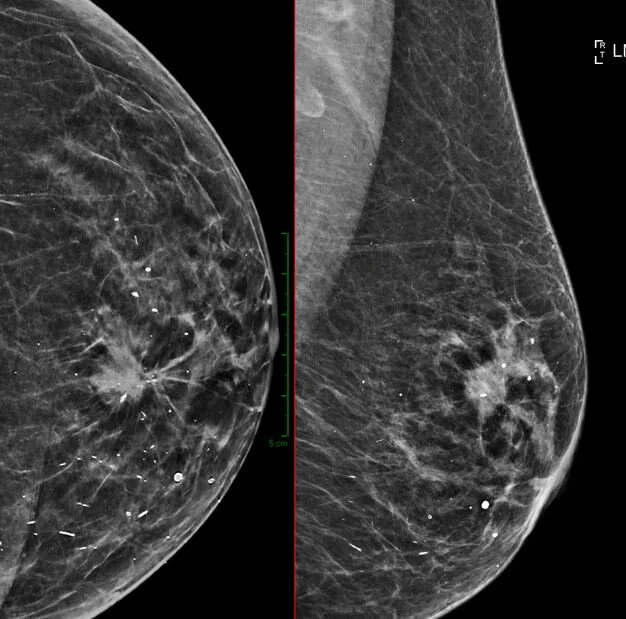

NEW UPDATE: We have eventually obtained out license to install the new mammography unit and have since also submitted all our quality assurance testing. As such we are now again able to provide a mammography service at our St Anne's branch! For more info or bookings phone 033 392 8800

Have you been referred for a breast biopsy? Has your mammogram showed a suspicious lesion? Visit http://www.xraypmb.co.za/s/Image-guided-breast-biopsy-short… to learn more about how we do image guided breast biopsies.